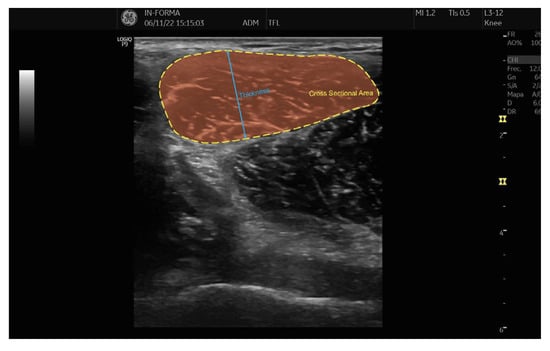

2.3. Measurement Protocol